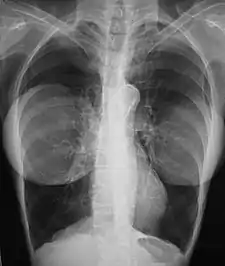

Chest X-ray showing breast implants

In the 1990s, the national health ministries of the listed countries reviewed the pertinent studies for causal links among silicone-gel breast implants and systemic and diagnosed autoimmune diseases and breast cancer.[72][37][73]  A study by researchers at the U.S. National Institute of Health reported an increase in four types of cancer among women with breast implants compared to other plastic surgery patients of the same age and similar demographic traits and health habits.[16] This increase in cancer was attenuated but did not disappear when the researchers followed the women for 5 more years, with a 43% increase in brain cancer and a 63% increase in respiratory cancer compared to other plastic surgery patients.[74]  A study by Watad et al. evaluated the medical records of more than 24,000 women with breast implants compared to more than 98,000 women with the same demographic traits who did not have breast implants. The researchers found a statistically significant 22 percent increase in several diagnosed diseases, increasing to more than 60% for Sjogren's syndrome, multiple sclerosis, and sarcoidosis[30] After investigating this issue, in 2021 the U.S. FDA revised its "black box warnings" on breast implants to acknowledge the association between breast implants and systemic autoimmune, rheumatologic, and neurological symptoms to state: "Patients receiving breast implants have reported a variety of systemic symptoms, such as joint pain, muscle aches, confusion, chronic fatigue, autoimmune diseases, and others. Individual patient risk for developing these symptoms has not been well established. Some patients report complete resolution of symptoms when the implants are removed without replacement".[75]